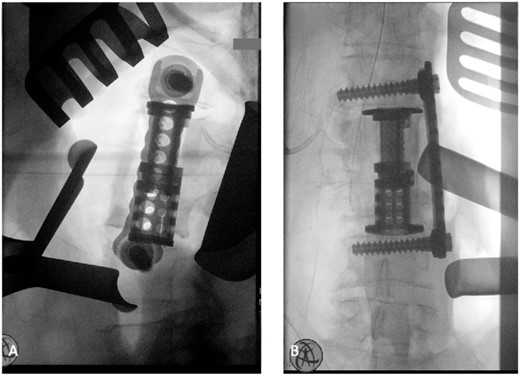

The patient was placed in the operating room for anterior lumbar interbody fusion via thoracoabdominal (TA) incision for retroperitoneal exposure. The patient was placed in the right-lateral decubitus position. The 10th rib interspace was identified, and a curvilinear incision was made from the midaxillary line and extended anteriorly and inferiorly toward the umbilicus. The retroperitoneal plane was entered, and the 11th rib was cut and morcellated for lumbar cage placement. The diaphragm was divided radially with electrocautery to further expose the abdominal cavity and retroperitoneal space. The lateral border of the psoas muscle was exposed and dissected into the anterior vertebrae L1–L4. The aorta and abdominal viscera were retracted toward the patient’s right side using an Omni retractor. Copious necrotic tissue and caseating granulomas were removed. The L2–L3 vertebrae were exposed, corpectomy was performed, and a titanium cage was placed with a plate spanning from L1 to L4 (Fig. 2A and B). To achieve added stability, a second surgery for posterior percutaneous screw placement without lumbar fusion was performed (Fig. 3). The patient recovered without complications and was subsequently discharged to a skilled nursing facility, and ultimately home. At the 1-month follow-up visit, the patient’s TA incision had completely healed, and there was no evidence of recurrent infection.

(A) Anterior intraoperative fluoroscopy demonstrating final titanium cage placement spanning from L1 to L4. (B) Lateral intraoperative fluoroscopy demonstrating final titanium cage placement spanning from L1 to L4.